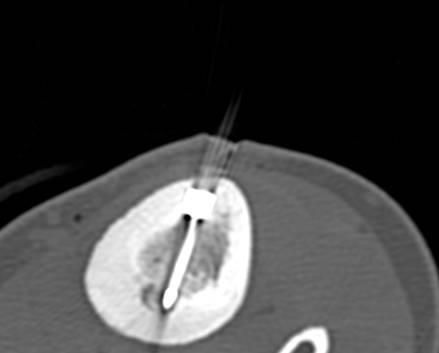

Eine Voraussetzung für die vollständige chirurgische Entfernung von Knochen- und Weichteiltumoren ist die präzise Erkennung der Tumorausdehnung und der Tumorgrenzen. Mit der Kernspintomographie (MRT) kann das Tumorgewebe exzellent von gesundem Gewebe abgegrenzt werden und somit die Ausdehnung vor der Operation bestimmt werden. Nach der kernspintomographischen Bestimmung der Tumorausdehnung werden unter kontinuierlicher MRT-Bildgebung die Grenzen des Tumors markiert. Die Marker werden mit einer Nadel ins angrenzende gesunde Gewebe eingebracht. Die Markierung kann am Tage vor der Operation durchgeführt werden. Alternativ ist die Tumormarkierung auch mit anderen bildgebenden Verfahren möglich, z.B. mit der Computertomographie oder dem Ultraschall.

Abbildung: Bei diesem Patienten wurde ein im Röntgen nur schlecht sichtbarer Knochentumor vor der Operation unter MRT-Kontrolle mit kleinen röntgendichten Spiralen („Coils“) markiert. Damit hat der Operateur eine optimale Darstellung des Tumorbereichs bzw. der Tumorgrenzen und kann gezielter, schonender und effektiver operieren.